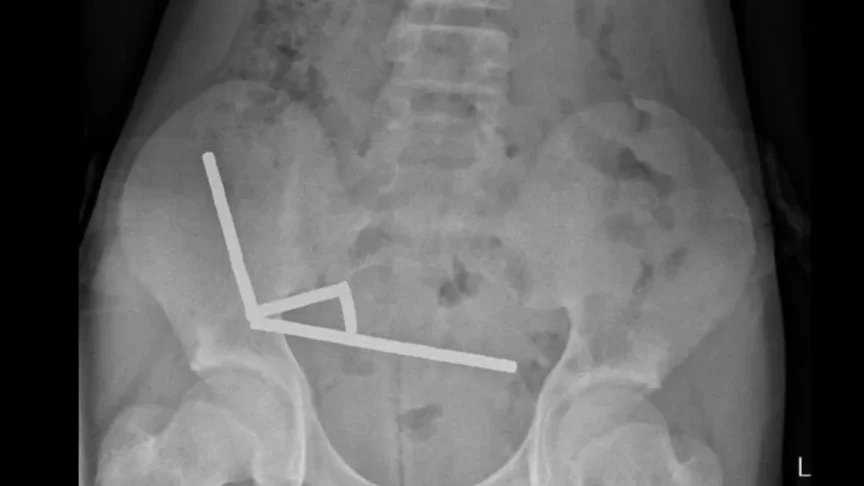

Рентгенівський знімок показав, що магніти згрупувалися разом у чотири прямі лінії всередині кишківника дитини. «Здавалося, що вони розташовані в окремих частинах кишківника, скріплених разом завдяки магнітним силам», — зазначили у лікарні.